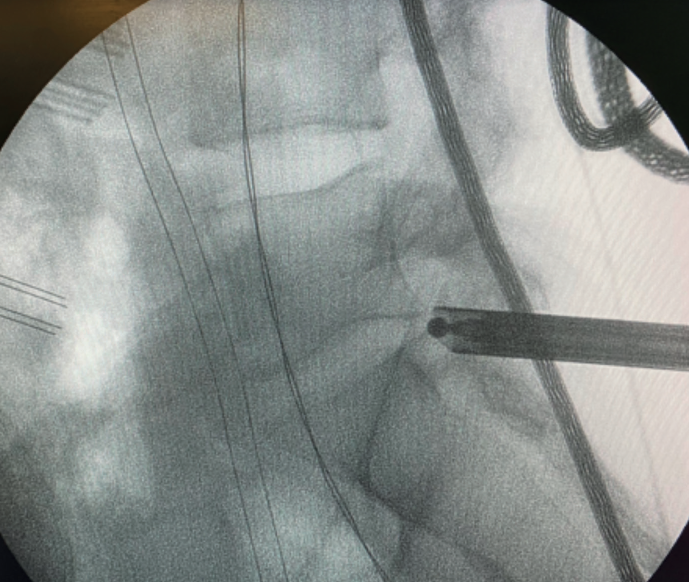

Figure 4. Radiological view of contralateral single-portal transforaminal endoscopy extending to the foramen, showing the capacity of endoscopy to treat contralateral disease in experienced hands.